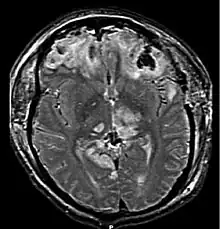

With increasing pressure and progression of the hernia there will be distortion of the brainstem leading to Duret hemorrhages (tearing of small vessels in the parenchyma) in the median and paramedian zones of the mesencephalon and pons. The rupture of these vessels leads to linear or flamed shaped hemorrhages. The disrupted brainstem can lead to decorticate posture, respiratory center depression and death. Other possibilities resulting from brain stem distortion include lethargy, slow heart rate, and pupil dilation.[9]

Central herniation

In central herniation, the diencephalon and parts of the temporal lobes of both of the cerebral hemispheres are squeezed through a notch in the tentorium cerebelli.[8][11] Transtentorial herniation can occur when the brain moves either up or down across the tentorium, called ascending and descending transtentorial herniation respectively; however descending herniation is much more common.[1] Downward herniation can stretch branches of the basilar artery (pontine arteries), causing them to tear and bleed, known as a Duret hemorrhage. The result is usually fatal.[11] Other symptoms of this type of herniation include small, fixed pupils with[12] paralysis of upward eye movement giving the characteristic appearance of "sunset eyes". Also found in these patients, often as a terminal complication is the development of diabetes insipidus due to the compression of the pituitary stalk. Radiographically, downward herniation is characterized by obliteration of the suprasellar cistern from temporal lobe herniation into the tentorial hiatus with associated compression on the cerebral peduncles. Upwards herniation, on the other hand, can be radiographically characterized by obliteration of the quadrigeminal cistern. Intracranial hypotension syndrome has been known to mimic downwards transtentorial herniation.